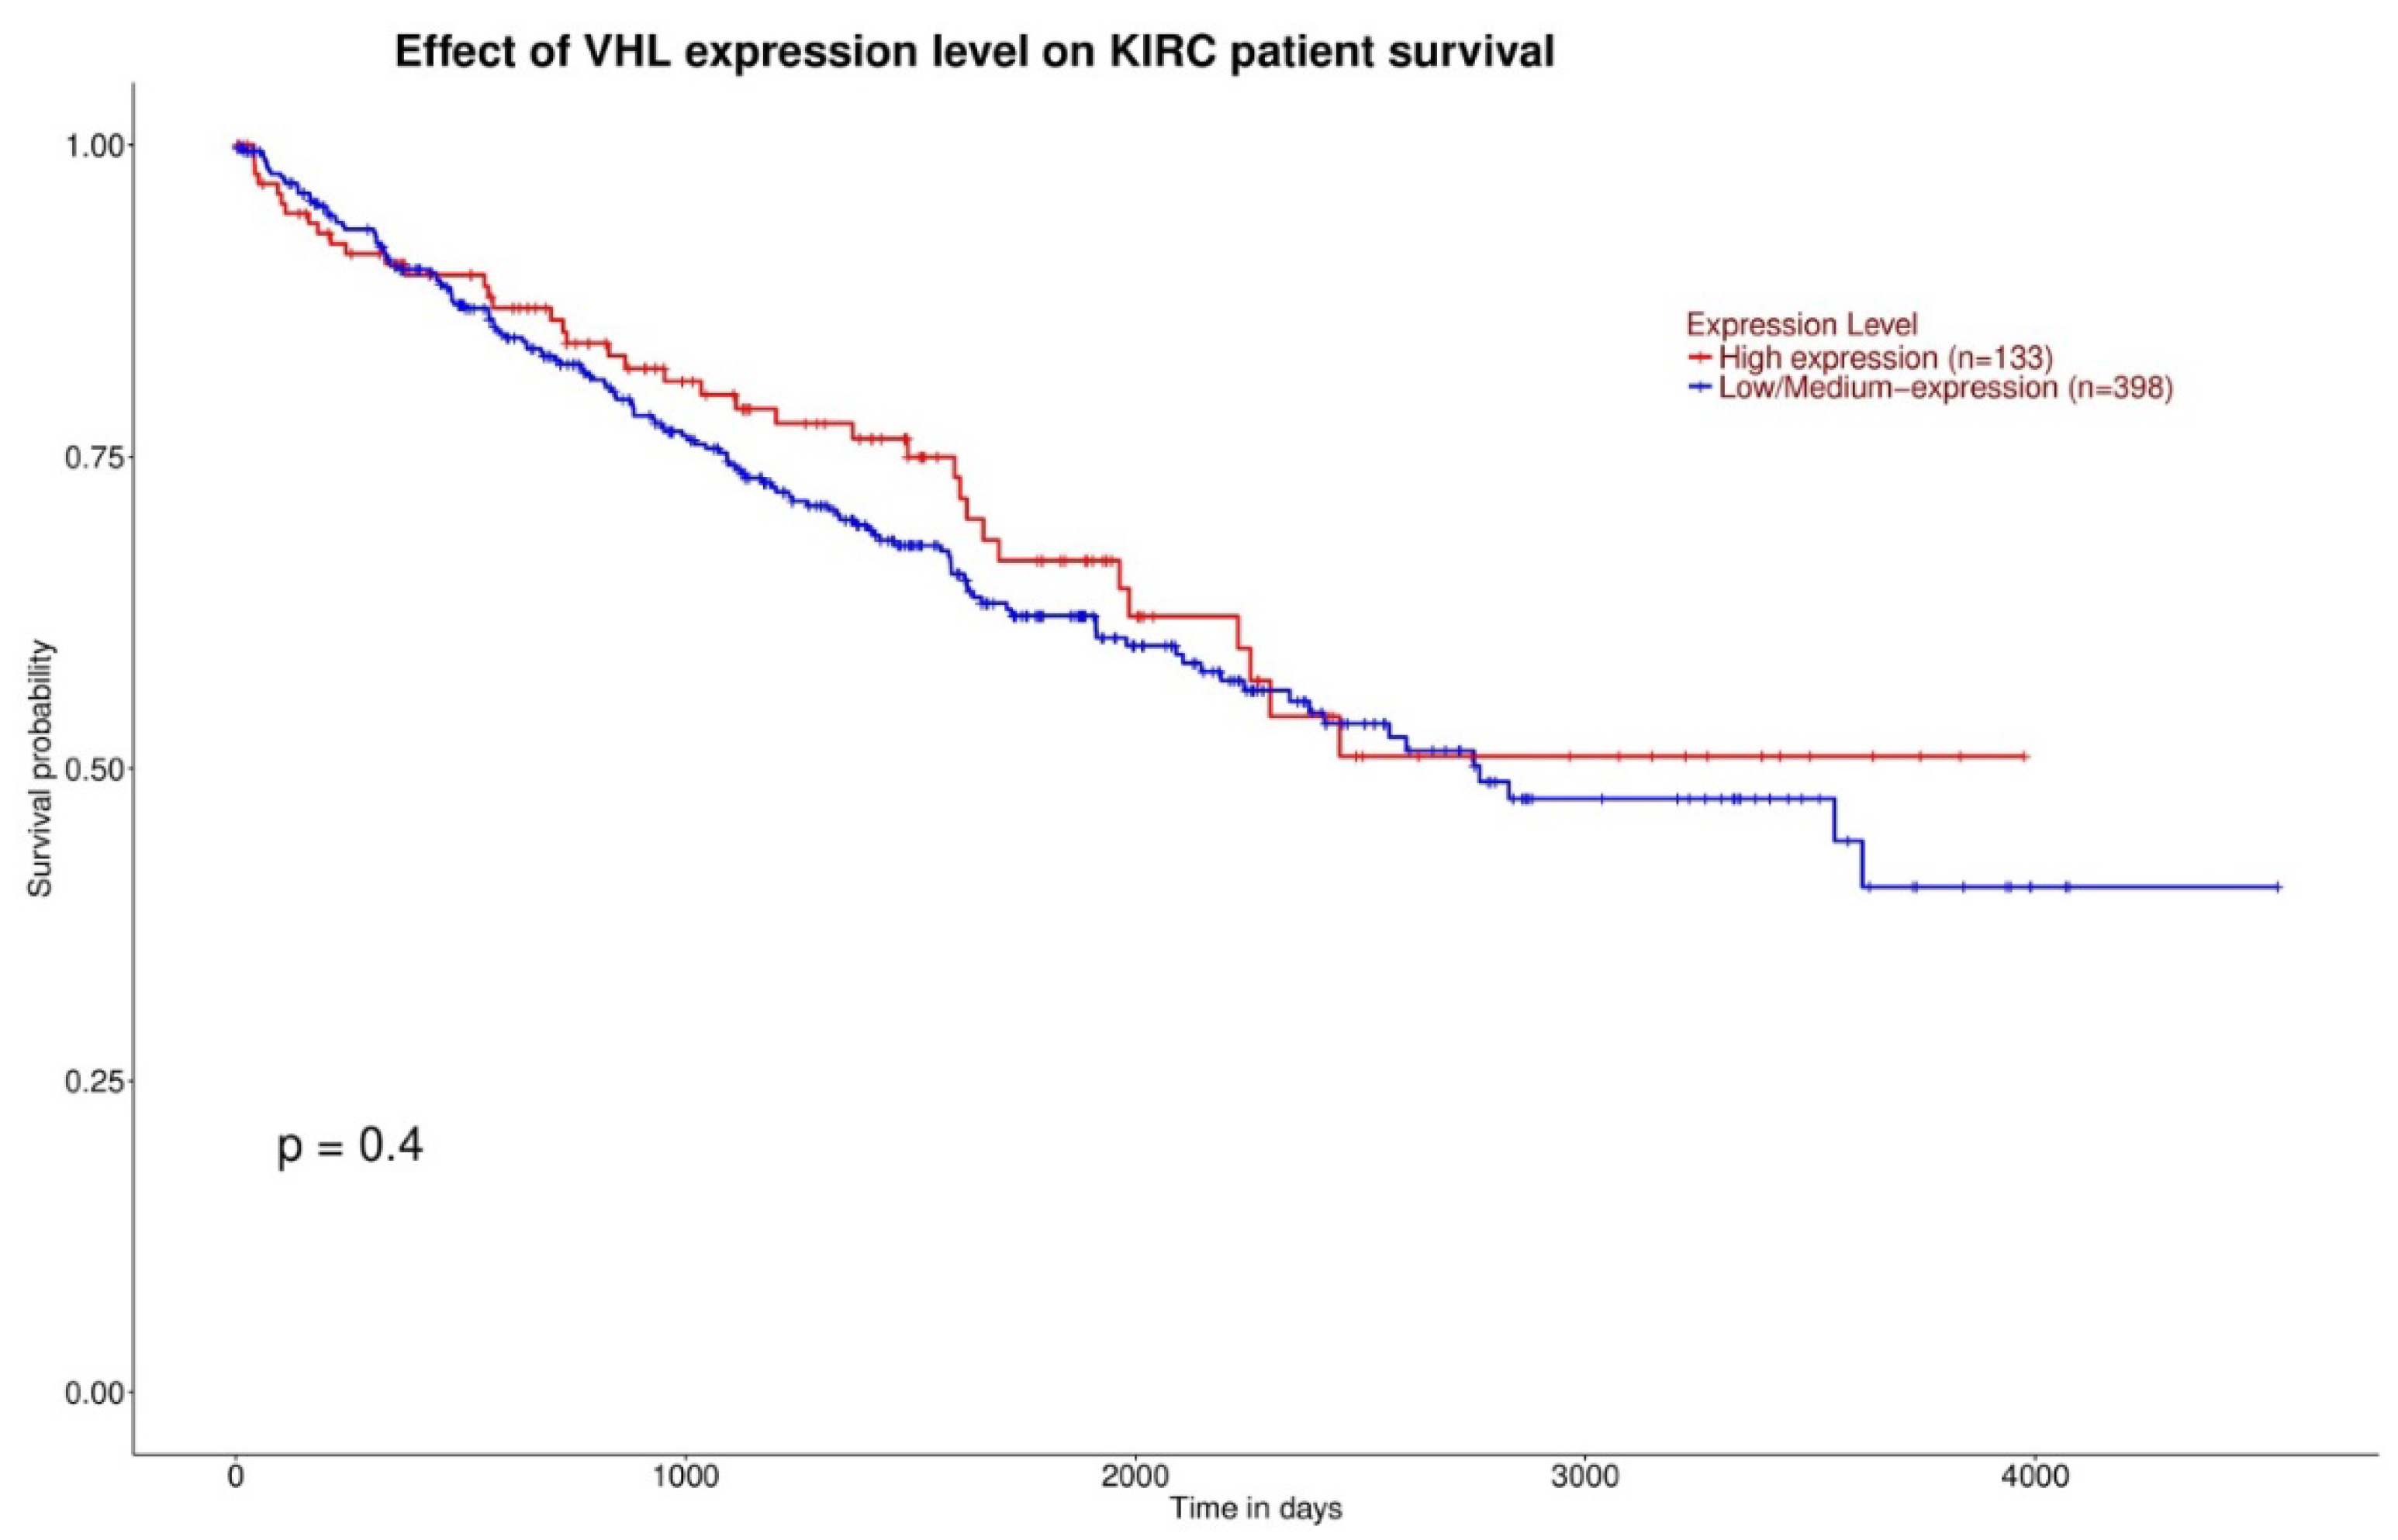

3.1. Gene Expression and Survival